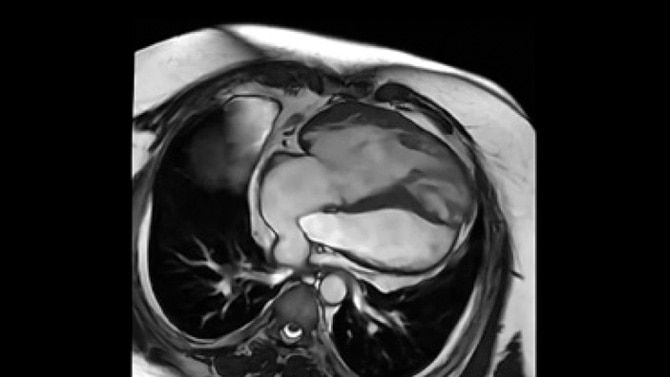

Enabling personalized oncology treatment with MRI

Our goal is to help you personalize cancer diagnosis, radiation therapy planning and treatment assessment for every patient. To achieve this, we can provide advanced functional and metabolic imaging information with SIGNA™ PET/MR AIR™⁵ and ODEN* (Oscillating Diffusion Encoding). Our AIR™ RT Suite solution is easy to set up and helps ensure the proper positioning of each patient. And the 32-channel AIR™ Open Coils provide patient comfort while delivering a high signal-to-noise ratio.

Exclusive AI applications like AIR™ Recon DL and MR Contour DL*, our auto-organ segmentation application that generates contours of at-risk organs, provides speed, consistency and accuracy, enabling the delivery of precise radiation therapy treatments.⁶This advanced hardware runs on our latest MR 30 for SIGNA release, found across all of our SIGNA scanners. This platform features AIR Recon DL, our pioneering deep-learning-based reconstruction algorithm that enables you to achieve pin-sharp image quality quicker than ever before. This makes the SIGNA PET/MR AIR incredibly powerful.

*SIGNA™ MAGNUS and ODEN are 510(k) cleared with the FDA. Not yet CE Marked. Not available for sale in all regions.